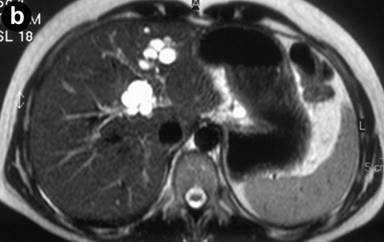

A 27-year-old female underwent a cholecystectomy for lithiasis. The patient was successively evaluated for diffuse and recurrent abdominal pain; no alcohol and/or smoking habits were reported. Laboratory measurements of total bilirubin and pancreatic amylases were unremarkable. Abdominal ultrasound was carried out which showed multiple hepatic and pancreatic cystic lesions; a dynamic enhanced CT scan confirmed the presence of multiple liver and pancreatic cystic lesions, but, in particular, the differentiation between simple hepatic cysts and cystic ectasia of the biliary ducts suggestive of Caroli’s disease was not reached. Therefore, MRI was requested to characterize the liver lesions and it was performed acquiring T1- and T2-weighted sequences integrated with T2-hydrographic images to specifically evaluate the biliary tract in axial and coronal views. MR cholangiography after intravenous administration of mangafodipir trisodium (Teslascan®, Nycomed, Amersham, Oslo, Norway), was also performed using T1-weighted sequences. Turbo spin echo T2-weighted images in axial and coronal views showed multiple hyperintense focal lesions in the left lobe of the liver, typical of cystic lesions, as well as multiple pancreatic cysts of the tail and saccular ectasia of the main biliary duct (Figure 1). T2-hydrographic dedicated images confirmed these findings, but certain imaging signs for a differential diagnosis between simple hepatic cysts and biliary cysts were not identified (Figure 2). However, the enhanced mangafodipir trisodium T1-weighted MRI clearly showed that some of the liver cysts concentrated mangafodipir trisodium contrast medium, thus demonstrating that these enhanced cystic lesions were in communication with the biliary ducts providing imaging criteria consistent with a diagnosis of Caroli’s disease (Figure 3). A segmental hepatectomy specimen demonstrated dilated simil-cystic intrahepatic ducts of the IV segment corresponding to a diagnosis of Caroli’s disease.

Figure 1. Conventional turbo spin echo T2-weighted axial (a., b. and c.) and coronal (d.) MR views show multiple cystic lesions in the left liver lobe as well as in the pancreatic tail. Saccular ectasia of the main biliary duct is also depicted. |